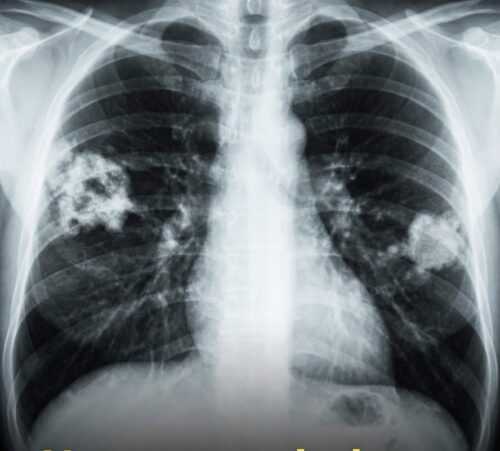

Sono gli effetti delle sigarette elettroniche. Ormai è noto a livello medico, e non solo. Le sigarette elettroniche aromatizzate causano danni polmonari permanenti

Negli Stati Uniti, molti adolescenti hanno sviluppato una patologia chiamata “polmone a popcorn” dopo aver svapato per vari anni. È una condizione che ti cambia la vita e, soprattutto, non ha una cura. Il nome medico è la bronchiolite obliterante, una patologia che danneggia le vie aeree più piccole dei polmoni, causando tosse cronica, respiro sibilante, estrema stanchezza e costante difficolta’ a respirare. Un tempo, il “polmone a popcorn” era collegato all’esposizione degli operai al diacetile negli impianti di produzione di popcorn per microonde. Ma oggi la preoccupazione si è spostata sulle sigarette elettroniche.

Il vapore delle sigarette elettroniche contiene una complessa miscela di sostanze chimiche. Molti aromi sono sicuri da mangiare, ma quando vengono riscaldati e inalati, diventano pericolosi. Danneggiano direttamente il tessuto polmonare ed entrano nel sangue senza alcun filtro. Le svapo sono diventate particolarmente popolari tra gli adolescenti, soprattutto per i gusti dolci e fruttati.

Ed è qui che il rischio aumenta. Più di 180 agenti aromatizzanti vengono utilizzati negli e-liquidi. Se riscaldate, possono formare composti tossici. Sebbene il diacetile sia stato rimosso da alcuni prodotti, sostituti come l’acetoina, anche questi potrebbero essere altrettanto dannosi. Quando queste sostanze chimiche vengono svapate, raggiungono i polmoni e altri organi in pochi secondi. Gli studi dimostrano che i giovani che svapano segnalano più problemi respiratori, anche rispetto ai fumatori. Ci vogliono normative più severe, etichette più chiare, test migliori e educazione sanitaria. Svapare può sembrare più sicuro che fumare.

Ma l’inalazione di queste miscele chimiche può causare danni permanenti e ridurre l’aspettativa di vita. Il messaggio che svapare o fumare la sigaretta elettronica non fa male, e’ sbagliato!! Fanno male eccome!!